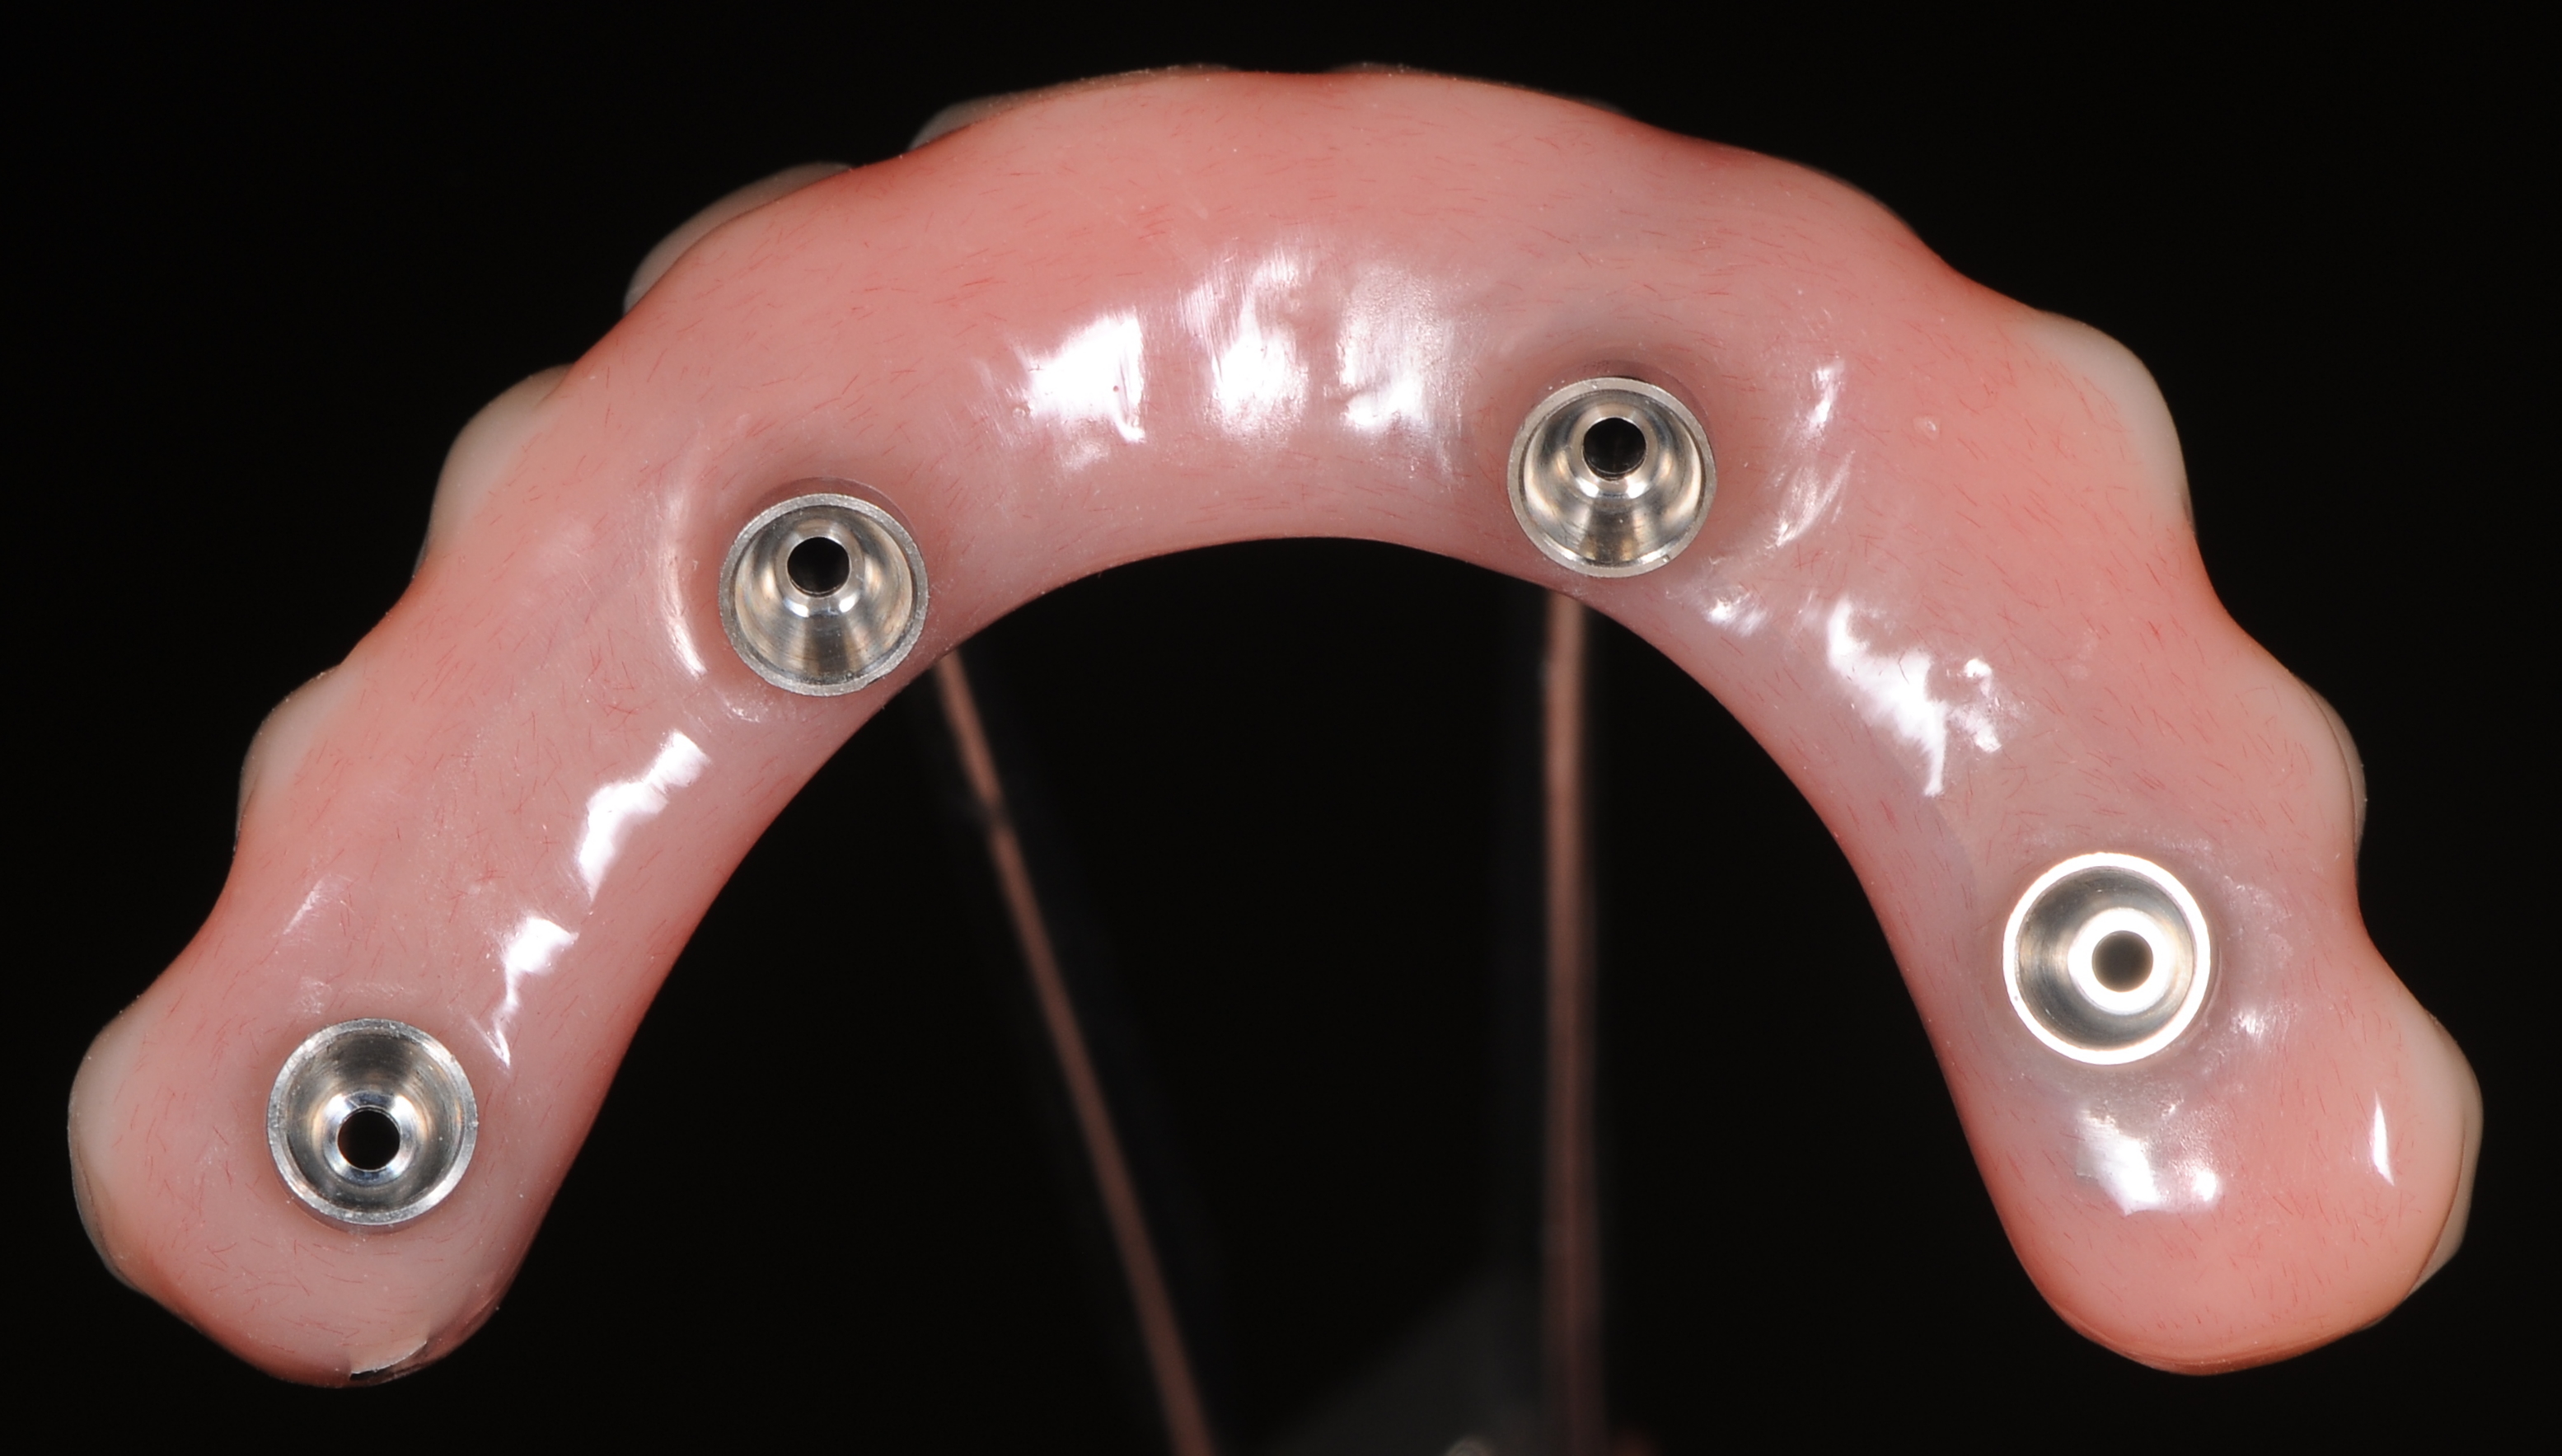

После окончание хирургического этапа в день операции был подготовлен временный условно-съёмный протез на имплантатах верхней челюсти для проведения точной перебазировки (рис 29,30).

Временные титановые цилиндры были зафиксированы к абатментам «Multi – unit» (рис. 31).

Фиксация титановых цилиндров к протезу проводилась прямым методом в полости рта пациента с помощью пластмассы холодного отверждения на основе полиметилметакрилатов (Tokuyama Rebase II), после припасовки протеза в полости рта, жидкую массу материала нанесли в шприце через тонкую канюлю в пространства между титановыми цилиндрами и ранее подготовленными отверстиями протеза. Первые минуты после нанесения пластмассы, проверяли правильного положения протеза в прикусе и держали протез нужном положении до полной первичной полимеризации нанесённой пластмассы. Когда материал полимеризовался, развинчивали конструкцию из полости рта пациента и удостоверились надёжности фиксации титановых цилиндров к протезу, затем дезинфицировав конструкцию зафиксировали к протезу титановые аналоги имплантатов к «Multi – unit» абатментам и передали конструкцию зубному технику для перебазирования и армирования протеза непрямым методом в лаборатории (рис. 32,33).

Зубной техник с протеза отливал модель с новыми десневыми контурами и положениями установленных имплантатов. После этого отделив титановые цилиндры от протеза зафиксировал их в модели к аналогам имплантатов.

Армирование протеза проводилось с помощью специальных титановых балок «TiRebar». Титановые балки с помощью композита фиксировались к титановым цилиндрам (рис. 33).

После полимеризации композита откручивались винты и проверялась пассивная посадка титановой балки к аналогам имплантата. Уже после этого зубной техник припасовывал акриловый протез к модели и перебазировал с пластмассой холодного отверждения на основе полиметилметакрилатов. После полимеризации протеза сошлифовали небную пластинку и излишки базиса с вестибулярной поверхности, при этом придесневая поверхность протеза оставалась относительно выпуклой или плоской , чтобы в дальнейшем не препятствовать осуществлению самостоятельной гигиене полости рта пациента (рис.34,35).